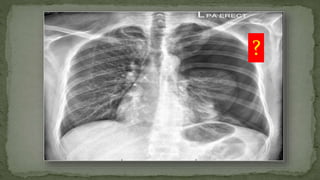

Left Pneumothorax

?

Right Pneumothorax